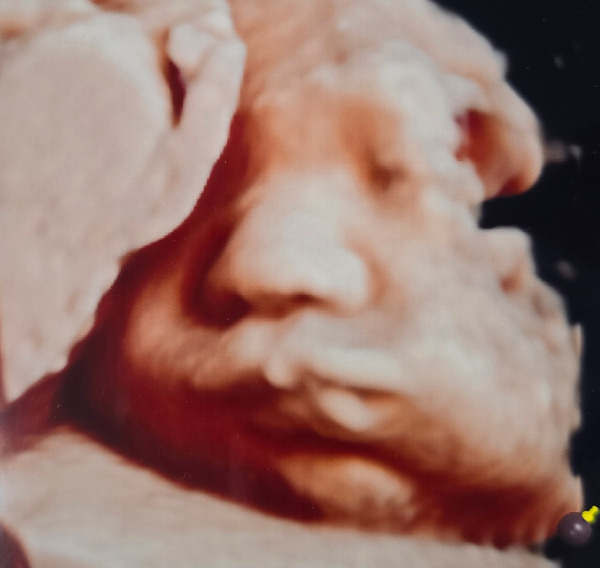

임신 중반을 지나면서 아내의 배가 점점 불러왔다. 여전히 입덧이 있었지만 초기보다는 많이 나아져서 먹을 수 있는 음식도 많이 늘어났다. 계속 줄어들기만 하던 몸무게도 양수와 둥글이의 영향인지 다시 늘기 시작했다. 27주 차에 두 번째 입체초음파 검사를 하였다. 입체 초음파 검사는 일반 초음파와 달리 아이의 형상을 3D 입체 영상으로 확인할 수 있는 검사다. 이미 12주 차 첫 번째 입체초음파 검사를 했었는데, 이때는 둥글이의 머리통과 팔다리 형상만 겨우 구분할 수 있었다. 그런데 두 번째 입체초음파 검사는 달랐다. 우리 부부는 이날 둥글이의 얼굴을 처음으로 선명하게 보았다.

1-10.jpg

1-11.jpg

12주 차와 27주 차의 입체 초음파 사진. 한 화면에 들어오지 않을 만큼 컸다.

어느새 쑥쑥 자라 한 화면에 담을 수도 없는 둥글이는 슬며시 얼굴 반쪽을 내보여 주었다. 감고 있는 눈과 작은 코, 심통 난 듯 불퉁한 볼과 입까지... 마치 아이를 눈앞에 두고 있는 듯 생생한 모습이었다.